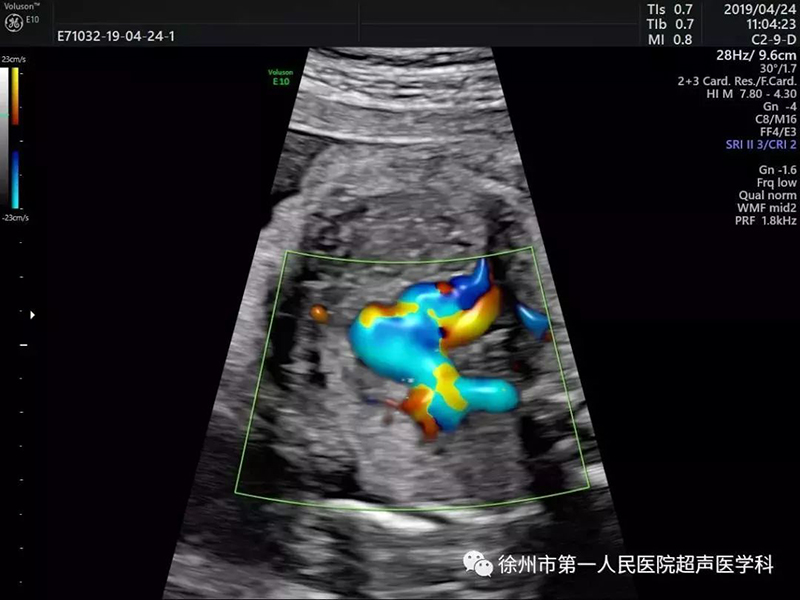

近日,徐州市第一人民醫(yī)院超聲醫(yī)學(xué)科引進(jìn)了高端婦產(chǎn)超聲專用機(jī)GE VOLUSON E10最新版本,實(shí)現(xiàn)了胎兒心臟超聲的立體血流、立體四維心臟結(jié)構(gòu)篩查,更好的助力胎兒先天性心臟病的檢查。

GE Voluson E10四維彩超 Voluson E10基于創(chuàng)新的“煊光”成像系統(tǒng)架構(gòu)平臺,以及首次搭載的煊影成像技術(shù)和煊流成像技術(shù),配合創(chuàng)新的電子曲面矩陣四維探頭EM6C(凸陣電子矩陣探頭),增加了噪聲消除、圖像增強(qiáng)、彩色和光照等特征,提供更多、更精準(zhǔn)的圖像數(shù)據(jù),引領(lǐng)婦產(chǎn)超聲進(jìn)入全新時代。

心臟超聲檢測對于超聲圖像質(zhì)量及輔助的診斷工具要求非常高。美國GE Voluson E10優(yōu)異的圖像分辨率,能在四維空間內(nèi)展現(xiàn)立體的心臟結(jié)構(gòu)和功能,能更精準(zhǔn)檢查胎兒心臟發(fā)育情況。

E10具備一整套卓越的胎心成像技術(shù)(STIC),支持從胎兒心臟結(jié)構(gòu)到心功能的分析,是胎兒心臟檢測評估領(lǐng)域的技術(shù)領(lǐng)導(dǎo)。雙平面成像技術(shù)可真實(shí)呈現(xiàn)胎心結(jié)構(gòu)、臍帶、血流變化,幫助臨床醫(yī)生及時作出確切診斷,是目前超聲領(lǐng)域診斷的利器。